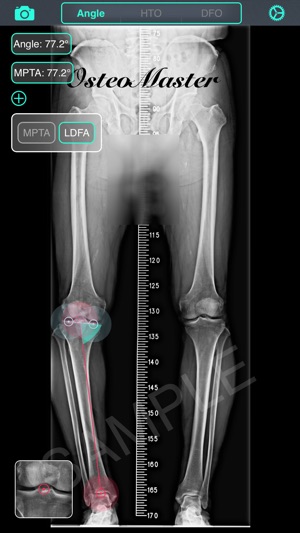

‎截骨神器 - 用于高胫骨截骨术(HTO)和股骨远端截骨术(DFO)的手术前术前规划工具。 特征: 1. 测量骨骼的解剖或力学軸角度,只需通过相机或照片库输入图像。 2. 计算术前负重线(WBL)和规划目标WBL。 3. 自动计算截骨矫正角度、楔块高度、切锯深度与脚长变化。 4. 设定期望WBL,矫正角度,缺口高度,MPTA或LDFA 5. 提供開放(open)或閉合(close)、内侧(medial)或外侧(lateral)截骨。 6. 模拟截骨调整后结果。 教学視頻:https://v.qq.com/x/page/h0527kc4vj1.html 簡体用户指南:http://pan.ba…